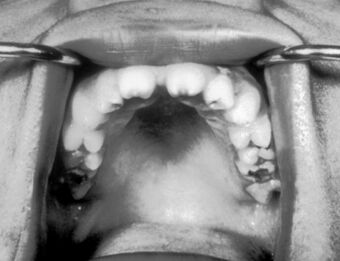

Hutchinson teeth congenital syphilis PHIL 2385.rsh.jpg

Notched incisors known as Hutchinson's teeth which are characteristic of congenital syphilis

• Blunted upper incisor teeth known as Hutchinson's teeth

A frequently-found group of symptoms is Hutchinson's triad, which consists of Hutchinson's teeth (notched incisors), keratitis and deafness and occurs in 63% of cases.[18]

• Hutchinson's triad, a set of symptoms consisting of deafness, Hutchinson's teeth (centrally notched, widely spaced peg-shaped upper central incisors), and interstitial keratitis (IK), an inflammation of the cornea which can lead to corneal scarring and potential blindness[citation needed]